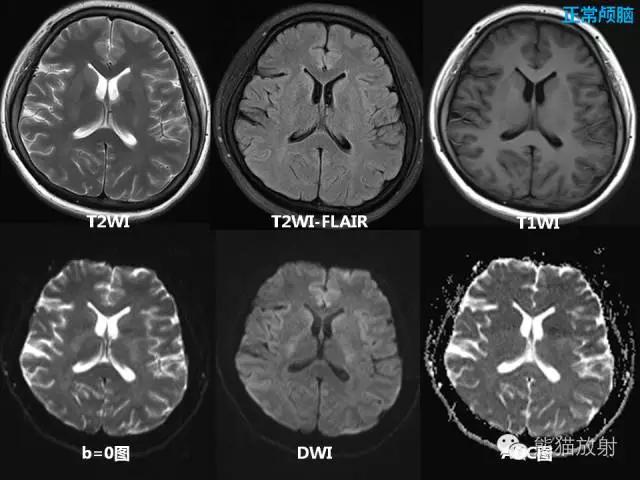

1、T1观察解剖结构较好。

2、T2显示组织病变较好。

3、水为长T1长T2,脂肪为短T1长T2。

4、长T1为低信号(暗),短T1为高信号(亮)。

5、长T2为高信号(亮),短T2为低信号(暗)。

6、水T1黑,T2白。

7、脂肪T1白,T2灰白。

T1加权成像、T2加权成像

所谓的加权就是“突出”的意思

T1加权成像(T1WI)----突出组织T1弛豫(纵向弛豫)差别

T2加权成像(T2WI)----突出组织T2弛豫(横向弛豫)差别。

在任何序列图像上,信号采集时刻横向的磁化矢量越大,MR信号越强。

T1加权像 短TR、短TE——T1加权像,T1像特点:组织的T1越短,恢复越快,信号就越强;组织的T1越长,恢复越慢,信号就越弱。

T2加权像 长TR、长TE——T2加权像, T2像特点:组织的T2越长,恢复越慢,信号就越强;组织的T2越短,恢复越快,信号就越弱。

质子密度加权像 长TR、短TE——质子密度加权像,图像特点:组织的 rH 越大,信号就越强;rH 越小,信号就越弱。脑白质:65 % 脑灰质:75 % CSF:97 %

脂肪、骨髓不论在T1WI、T2WI和PDWI(质子加权像)图像上均呈高信号